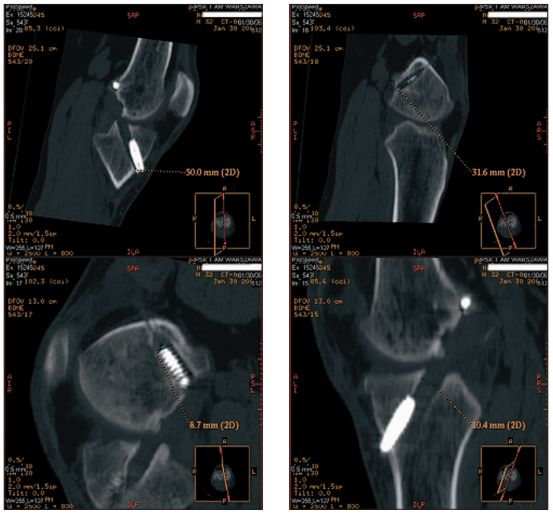

/ 8Badanie TK

Badanie TK, rekonstrukcja wielopłaszczyznowa (MPR)